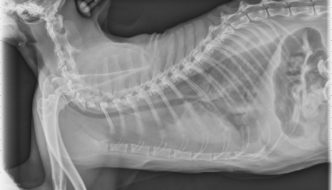

This week's case is a 10-year-old female neutered Siamese cat with 2-day history of labored breathing. Looking at the single image below, how would you describe this pattern? … [Read more...]